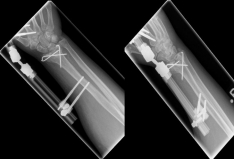

Complicated fractures involving the articular surface or dislocation should be surgically treated. Open fractures in which the skin is injured and bone is exposed require immediate surgical care. An involvement of the articular surface can lead to a restriction of the mobility in the wrist and therefore requires an anatomically exact reduction. The standard procedure for distal radius fractures is the provision of a titanium plate applied by the diffraction-side (palmar plate osteosynthesis) or the application of an external holder (external fixator).

Handgelenk 4    Handgelenk 5

Pictures: In this case, the articular surface of the wrist was completely destroyed, so that only a therapy by means of outer retainer and some K-wires to correct the position was possible. Here is a practice only after removal of the outer holder after 6-8 weeks possible. Such severe joint injuries often lead to premature joint wear